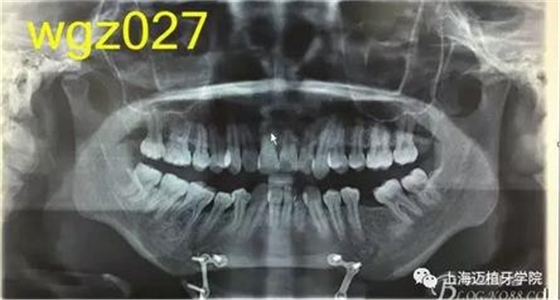

根據(jù)以下上傳的圖片及X線影像資料,你認(rèn)為她的牙齒存在什么問(wèn)題?應(yīng)該如何進(jìn)行矯治設(shè)計(jì)?

圖2

上海萬(wàn)眾醫(yī)院正畸科進(jìn)修醫(yī)生魏倩倩作業(yè)。 某女,25歲。 主訴:頦部術(shù)后自覺(jué)牙齒不齊,牙齒凸要求矯正。 既往史:曾有顳下頜關(guān)節(jié)疼痛史,于外院診斷為關(guān)節(jié)不可復(fù)性前移位伴髁突不對(duì)稱,行關(guān)節(jié)盤復(fù)位術(shù)。約3個(gè)月前在外院行頦成形術(shù),現(xiàn)因牙齒不齊,牙齒凸前來(lái)就診。 口外檢查:正面觀,長(zhǎng)面型,左右基本對(duì)稱,面下1/3過(guò)長(zhǎng),頦部明顯水腫,質(zhì)硬; 側(cè)面觀,面型稍凸。 顳合關(guān)節(jié)檢查:無(wú)壓痛,左側(cè)彈響,兩側(cè)髁突運(yùn)動(dòng)基本一致。 口內(nèi)檢查:恒牙列,下頜前庭處縫合,傷口愈合良好??谇恍l(wèi)生情況一般,牙齦紅腫,LR2、LL6缺失,UR456舌傾與LR67成反合關(guān)系,UR3頰側(cè)突出移位,UR2UL2近中扭轉(zhuǎn),UL1近中外翻唇傾,UR7UL7頰傾,LR6近中傾斜升高,LR5近中傾斜,LR4頰傾移位,LR3冠舌側(cè)傾斜,LL2近中扭轉(zhuǎn)冠頰傾,LL3舌傾,LL78近中傾斜。 模型分析:上頜前牙段擁擠度9.5mm,下頜前牙段擁擠度9mm,spee左右約3mm, LL5、LL7之間間隙約為5mm。上下中線右偏約1.5mm。全牙比約為80%,前牙比62%。磨牙關(guān)系:右側(cè)近中關(guān)系,UL6與LL7遠(yuǎn)中尖對(duì)尖。尖牙關(guān)系:右側(cè)遠(yuǎn)中關(guān)系,左側(cè)近中關(guān)系。 行為分析:患者已于外院行頦成形術(shù),面型已改善,但患者仍覺(jué)得牙齒凸,說(shuō)明患者非常重視面型問(wèn)題,對(duì)美觀要求高。 頭顱側(cè)位片:面型稍凸,上唇在E線前約1.5mm,下唇在 E前約1mm 。 SNA: 85↑ SNB: 75↓ANB: 10↑ U1-L1: 113.6↓ U1-SN: 107.9 L1-M P: 88 ↓Y軸角:65.8 FH-MP: 37↑ SN -M P: 45↑ 曲面斷層片:28顆恒牙,LL6缺失,牙槽骨均位于釉牙骨質(zhì)界以下,LR6、LL7近中牙槽骨角型吸收,頦部可見(jiàn)成型術(shù)鈦合板。左側(cè)升支較右側(cè)粗。 關(guān)節(jié)片:左右髁突不對(duì)稱,髁狀間隙右側(cè)明顯較左側(cè)寬,右側(cè)間隙清楚,大小勻稱 ,左側(cè)欠佳。 診斷:安氏3類 骨性2類 高角 上下前牙重度擁擠 中線不齊 間隙分析:下頜 , LL5與LL7之間的有5mm間隙,下頜擁擠度為9mm,整平下頜曲線需要約3mm間隙,下頜需要約12mm間隙,減去現(xiàn)有間隙還需要7mm間隙。上頜,擁擠度為9.5mm,擁擠主要集中在前牙段。 支抗分析:患者頦部術(shù)后仍覺(jué)面型凸(主要是上頜前突),所以除了要解決擁擠度外還需要內(nèi)收前牙,所以上頜需要強(qiáng)支抗?;颊逽NB為75,下頜發(fā)育不足,高角,相對(duì)低角病例來(lái)說(shuō),下頜磨牙較易前移。下頜前牙重度擁擠的情況下主張只解除擁擠不宜內(nèi)收(該患者系下頜后縮病例)。患者ANB為10°,本屬于正頜正畸聯(lián)合治療,現(xiàn)患者已做頦部成型術(shù),患者面型得到改善,故患者現(xiàn)在主要為解決擁擠,少量?jī)?nèi)收前牙,解決上前牙凸度。